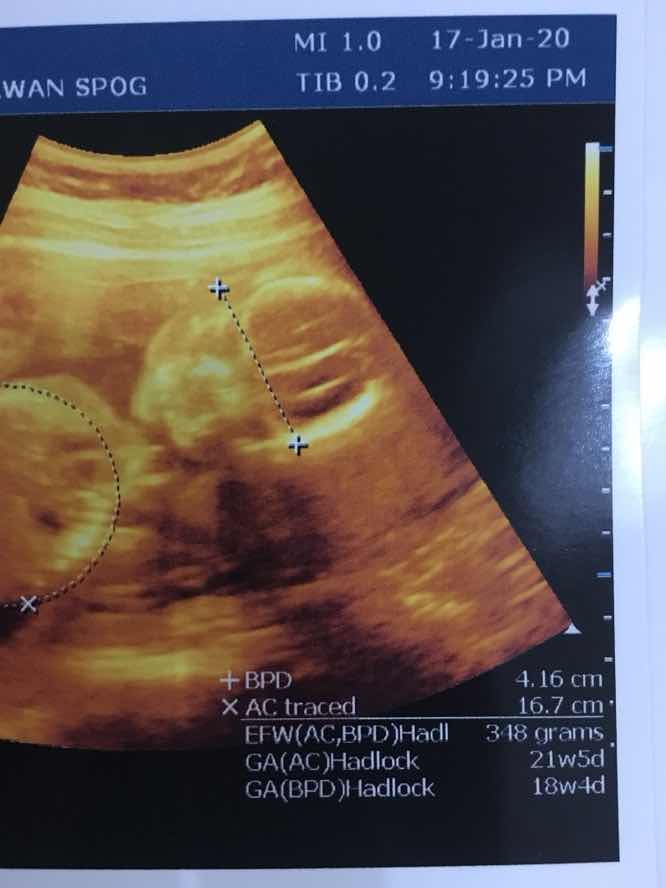

Di foto USG Di ujung kanan bunda Di situ tulis GA(AC) 21w5d GA(BPD) 18w4d Mau tau umur janinnya lihat yg mana satu ya bun?